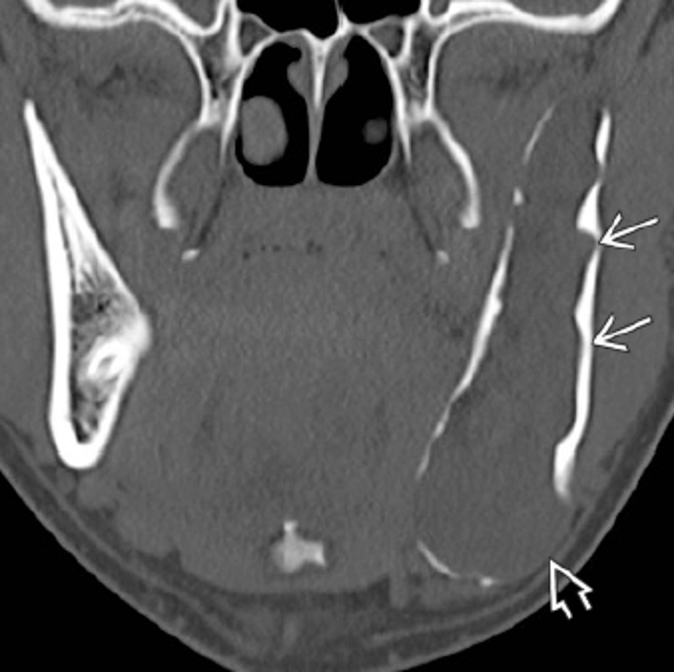

En estas imágenes te mostramos varios casos de la misma patología.

Participa describiendo la patología, dando diagnósticos diferenciales o cualquier comentario que sea útil.

Posterior a sus respuestas estaremos revelando los casos con su información en los comentarios.